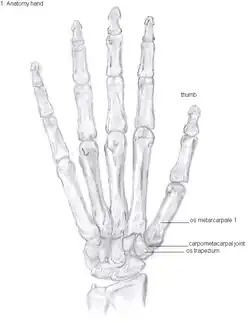

Anatomy

The TMC joint is a synovial joint between the trapezium bone of the wrist and the metacarpal bone at the base of the thumb. This joint is a so-called saddle joint (articulatio sellaris), unlike the CMC joints of the other four fingers which are ellipsoid joints.[17] This means that the surfaces of the TMC joint are both concave and convex.

This shape provides the TMC joint a wide range of motion. Movements include:[18]

The TMC joint is stabilized by 16 ligaments.[19] Of these ligaments, the deep anterior oblique ligament, also known as the palmar beak ligament, is considered to be the most important stabilizing ligament.[20]